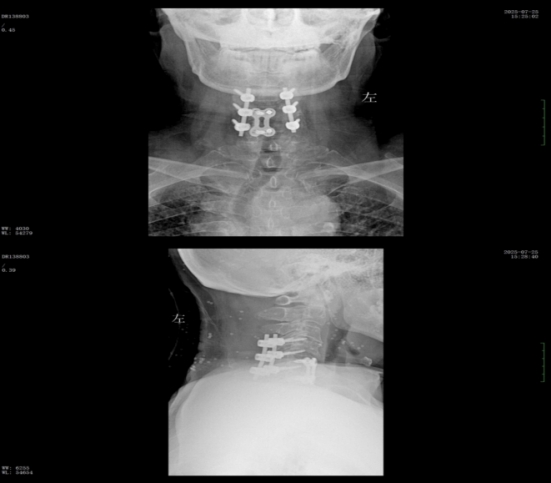

術(shù)前核磁共振提示:頸椎椎管狹窄、頸脊髓信號(hào)改變